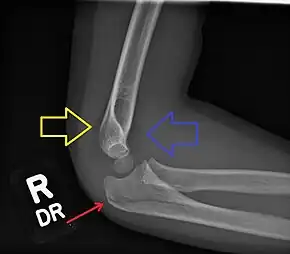

Fractured elbow in a child (ulnar shaft) with joint effusion of elbow

Normal elbow in same child, other side